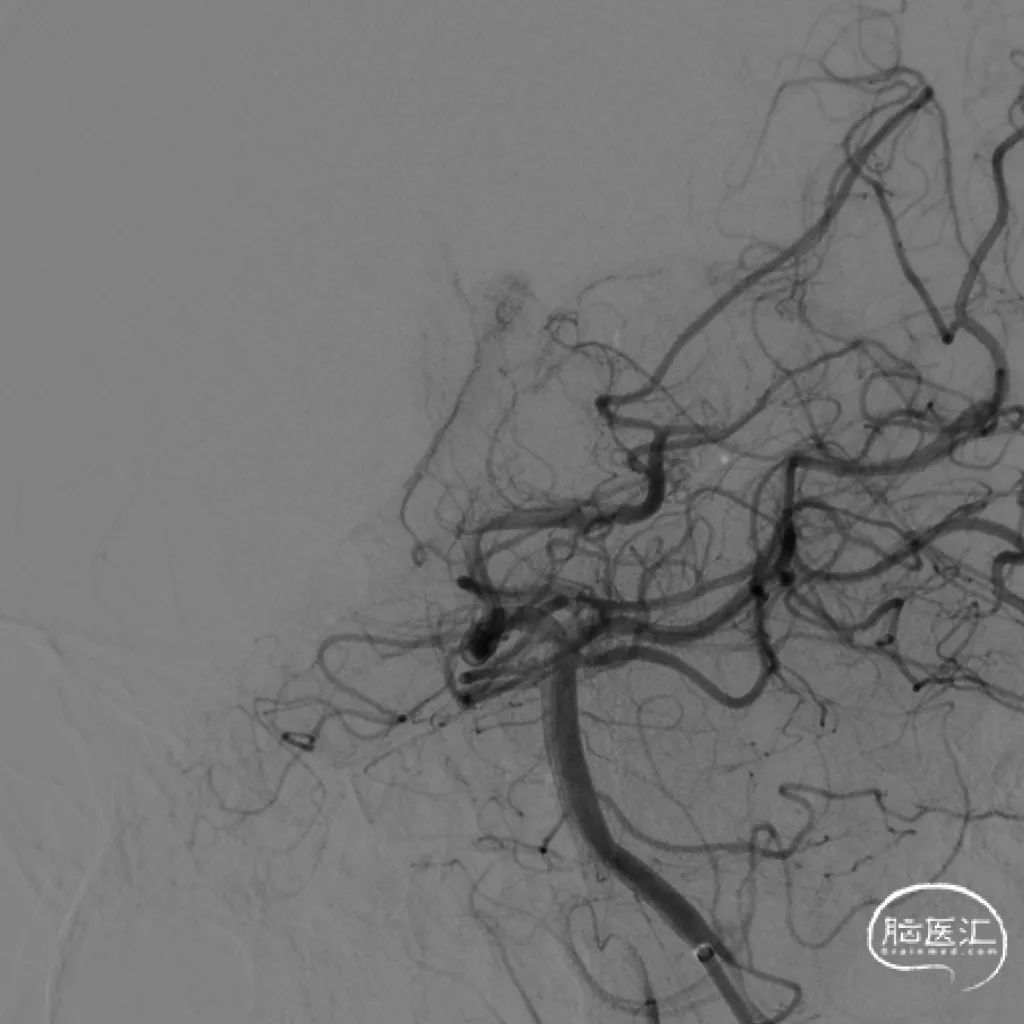

图2. DSA提示右侧脑室后角畸形血管团,由脉络膜后动脉供血。